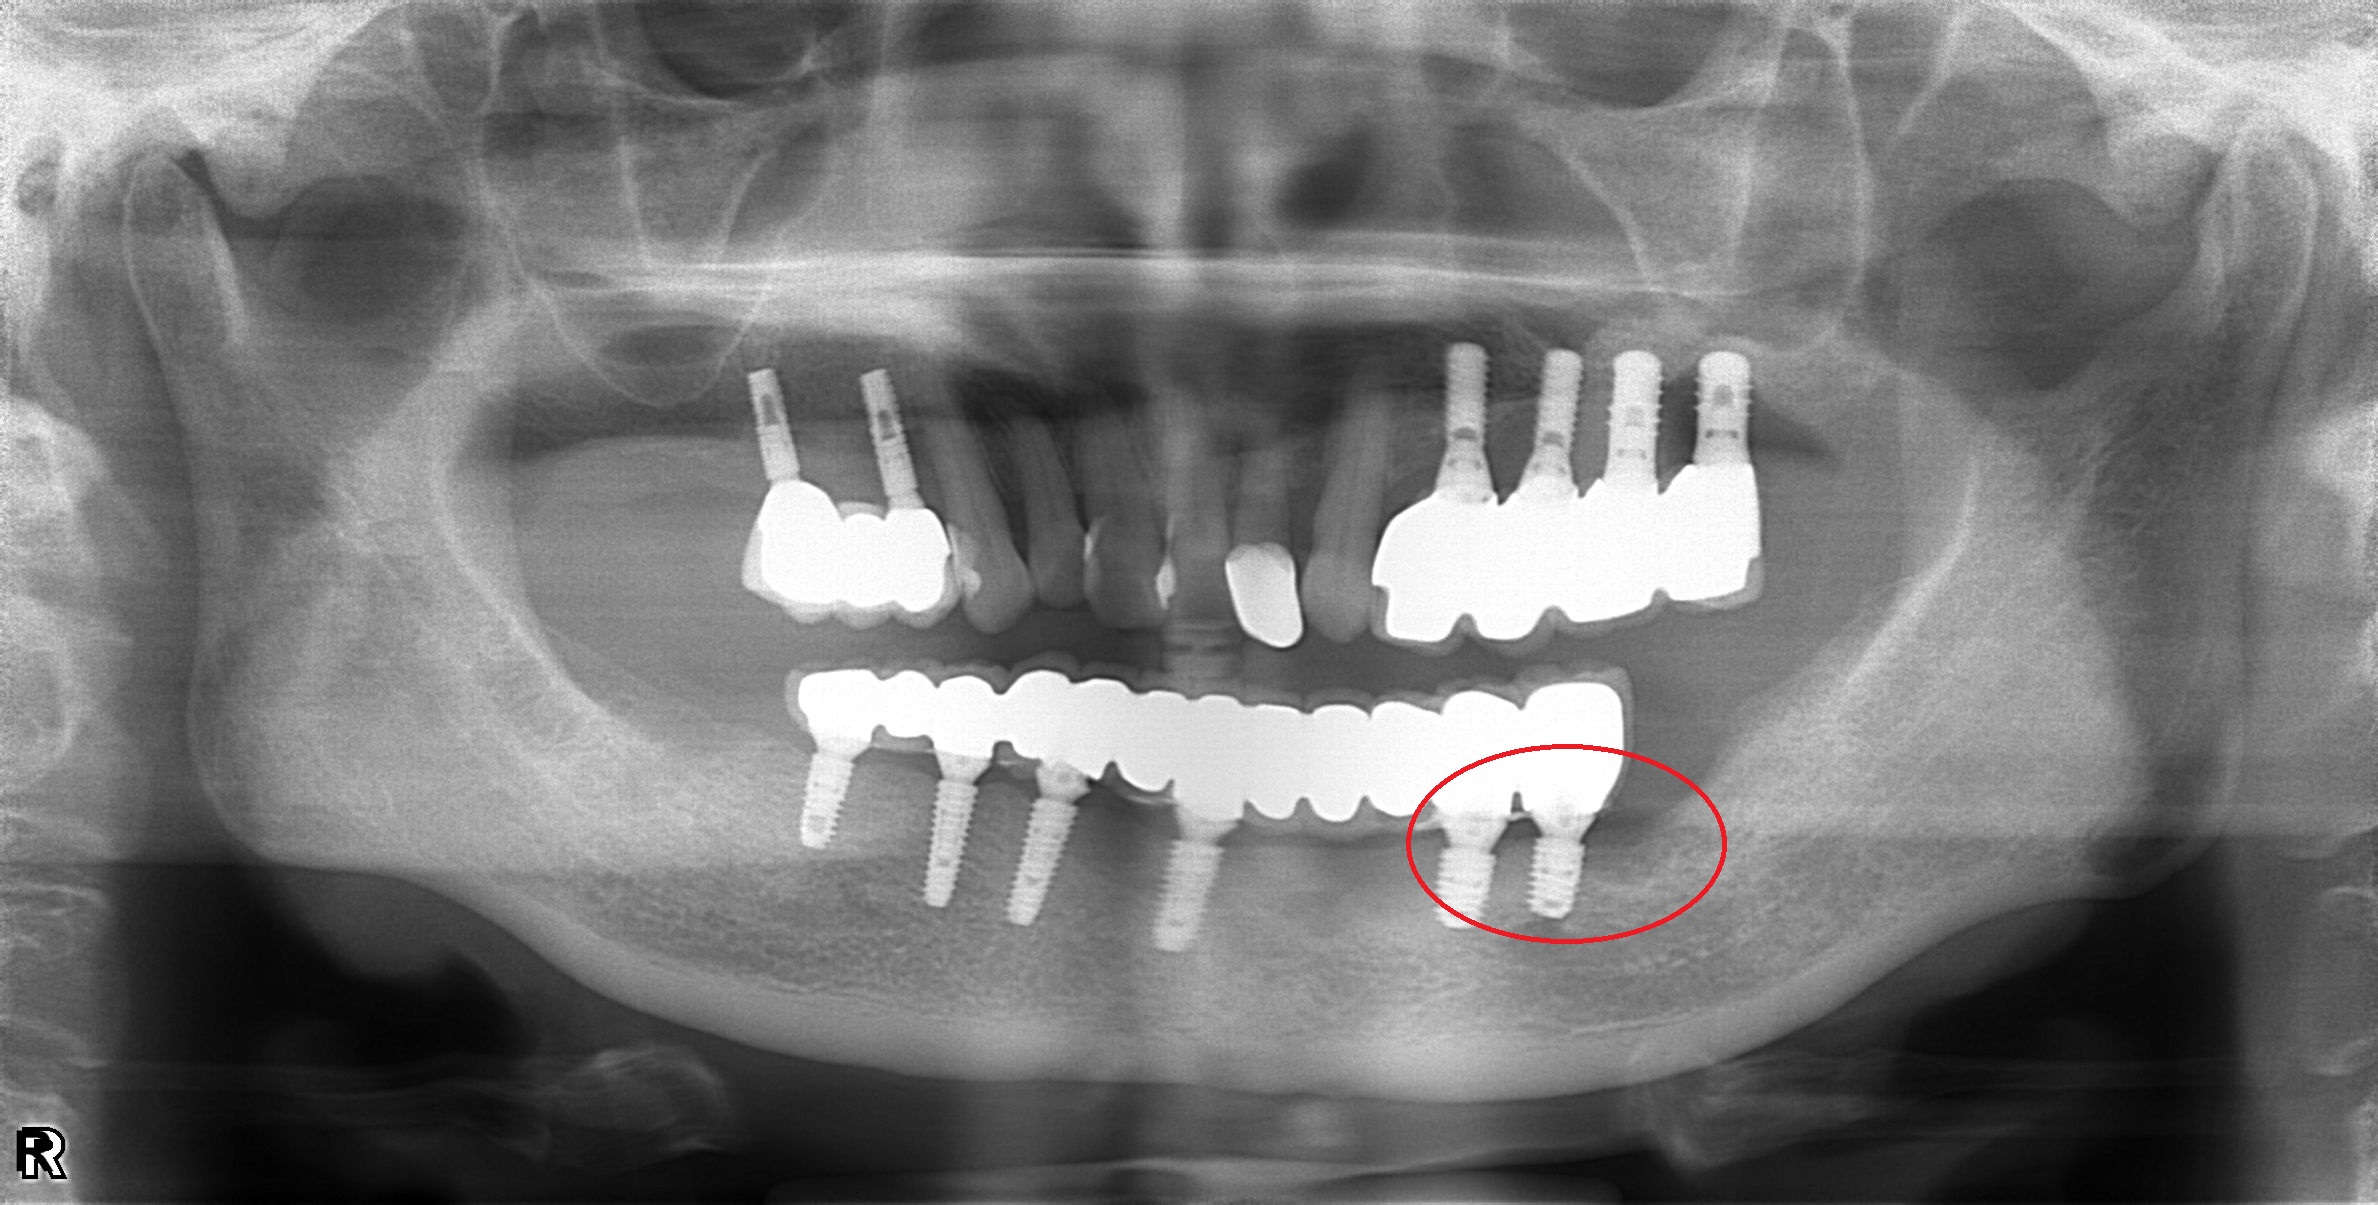

植體周圍炎處理

案例一